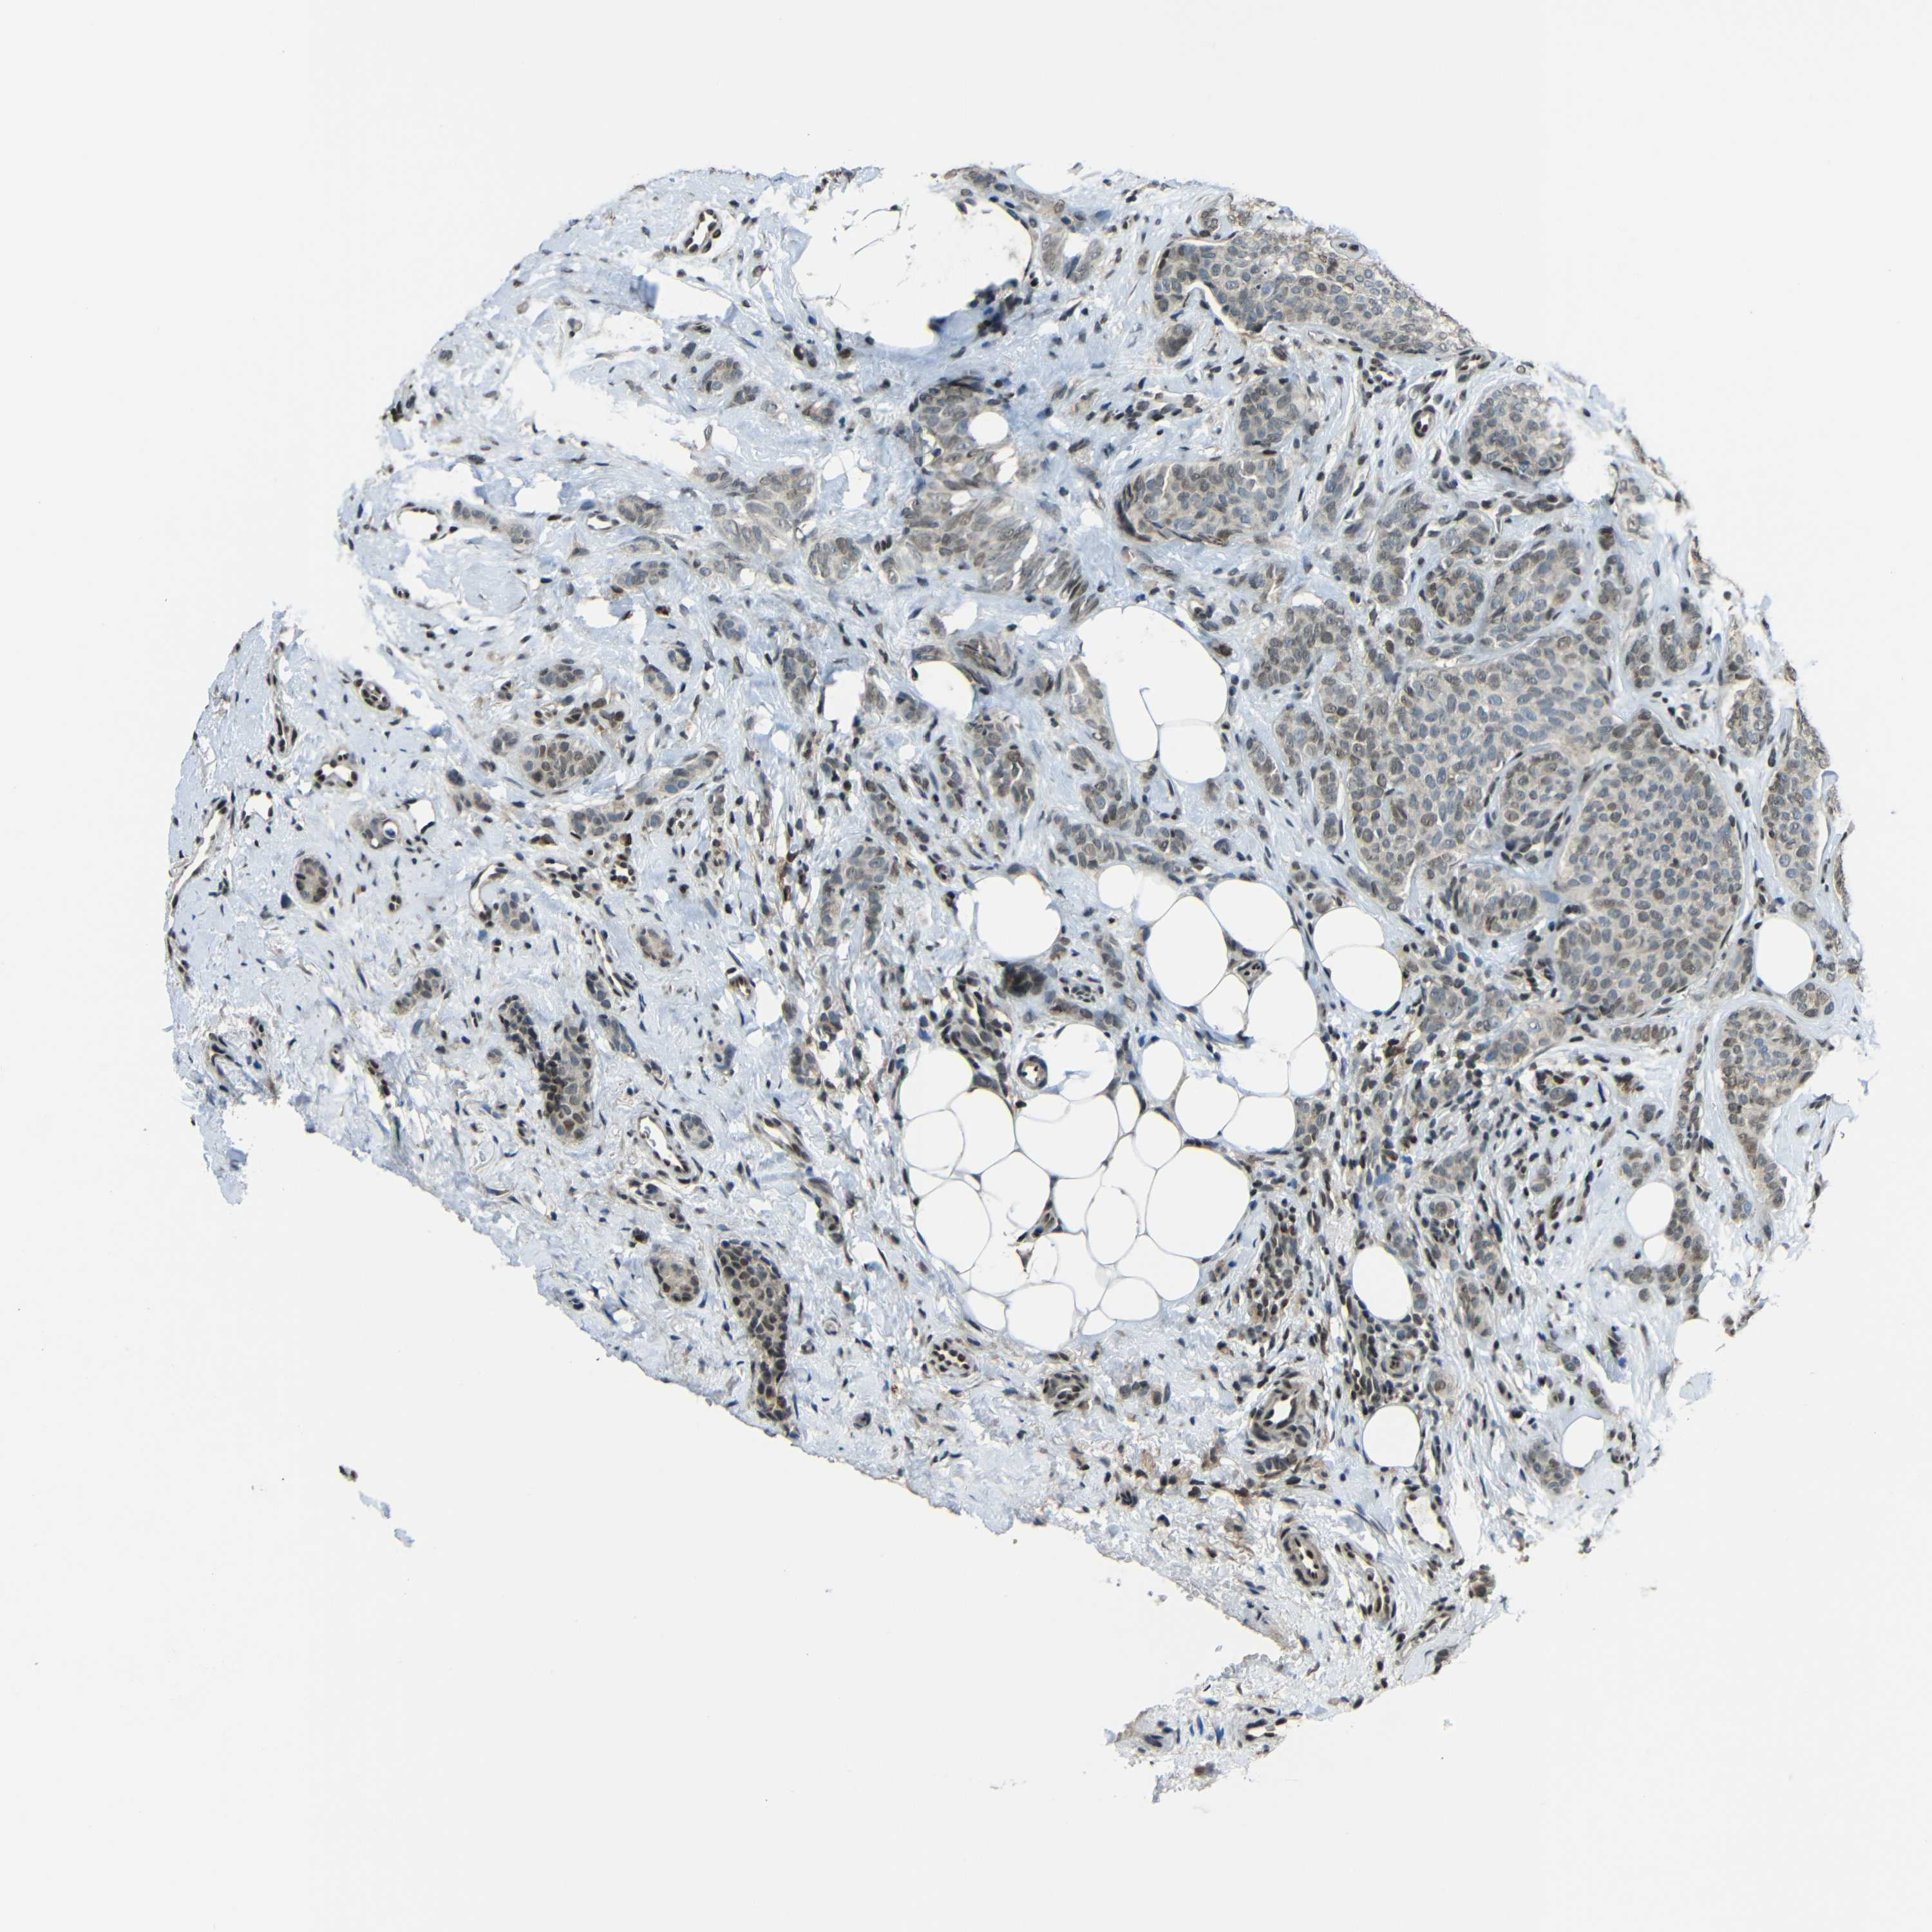

CANCER BREAST CANCER Show tissue menu

BRCA TCGA BRCA VALIDATION PROTEIN EXPRESSION